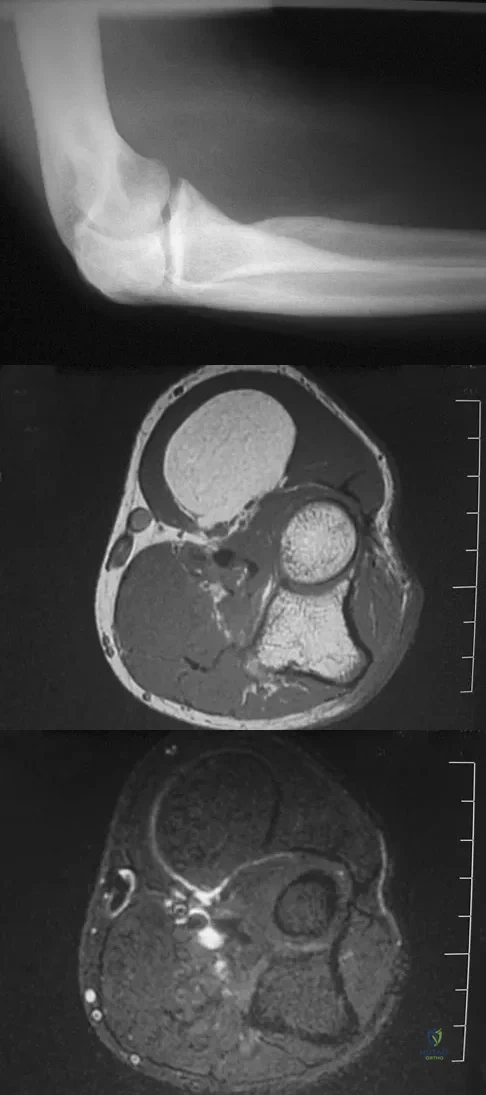

A 51-year-old male truck driver has had progressive left hip pain for more than 2 years, and he reports that the pain has become severe in the past 9 months. He is now unable to work because of the pain. Examination reveals that range of motion of the hip is limited to 95 degrees of flexion, 0 degrees of internal rotation, and 20 degrees of external rotation. The plain radiograph, MRI scan, and intraoperative gross photographs are shown in Figures 9a through 9d. Management should consist of

A 16-year-old boy has had left knee pain and swelling after sustaining a minor twisting injury while playing basketball 2 weeks ago. Figures 5a through 5e show the radiograph, MRI scans, and biopsy specimens. What is the most likely diagnosis?

A 65-year-old woman has had chronic aching discomfort involving her elbow for the past 6 months. Radiographs and a biopsy specimen are shown in Figures 38a through 38c. What is the most likely diagnosis?

Figures 10a through 10c show the plain radiograph and MRI scans of a 41-year-old man who has right hip pain. What is the most likely diagnosis?